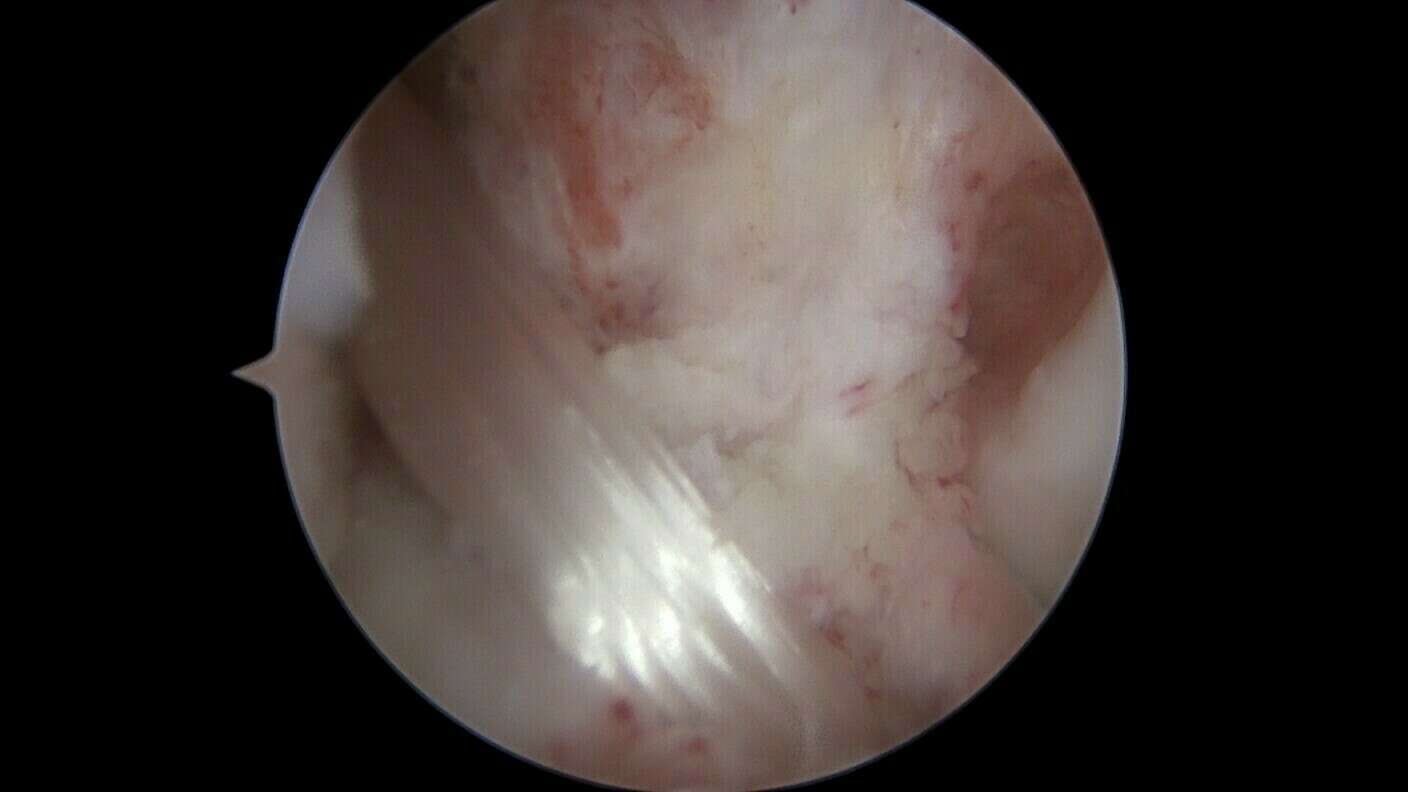

Galerie photo